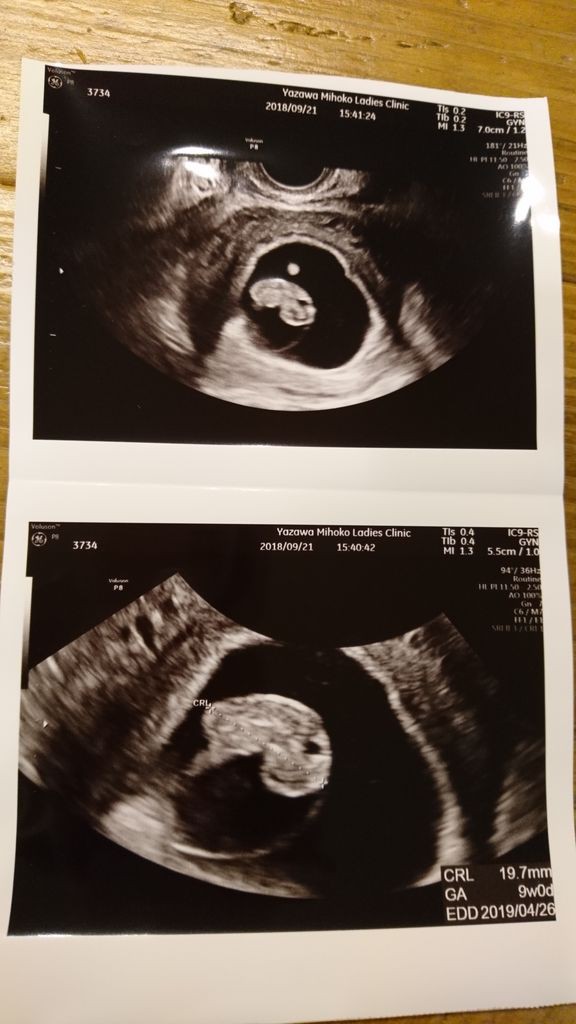

出産予定日と週数確定 9週の壁を越えました 妊娠3ヶ月 ポチレビュー